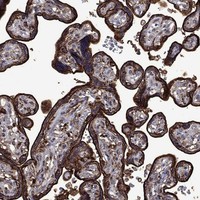

Immunohistochemical staining of human placenta shows strong cytoplasmic and membranous positivity in trophoblastic cells.